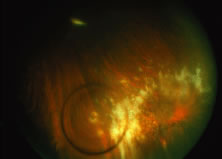

The ARN patient typically presents with progressive visual blurring in one or both eyes occurring over several weeks. These patients often are initially treated with corticosteroids, antitoxoplasmosis drugs, and other medications before arriving at the correct diagnosis. Examination reveals a prominent anterior uveitis that may be granulomatous or nongranulomatous (Fig. 1). Inflammatory signs may be prominent and cause severe pain (Fig. 2). The uveitis may be diffuse and so severe that it causes proptosis. These signs, and the diffuse vitreitis that makes the view of the retina difficult, may contribute to the high degree of delayed and/or misdiagnosis that occurs in the early stages of the disease. Significant vitreous cellular infiltration is seen in the presence of retinitis that is manifest by opacification of the retina, often most prominently in the periphery. Posterior pole involvement may include retinitis, as well as inflammation of the optic nerve head. Optic neuropathy might be the first sign of ARN with subsequent development of other retinal manifestations.8 Ultrasonography and computed tomography (CT) might be helpful in cases of ARN associated with optic nerve edema revealing enlargement of the optic nerve sheath.9 Even in ARN patients who are not immunocompromised and who have no clinical evidence of encephalitis, magnetic resonance imaging of selected cases has shown lesions of the lateral geniculate, optic tracts, and chiasma, which suggests that the virus spreads through the central nervous system (CNS) by axoplasmic transport from the retinal ganglion cells.10 A secondary retinal vasculitis is common, often accompanied by a mild number of retinal hemorrhages. Days to weeks after onset of the infection, the discrete peripheral lesions typically coalesce into a white or yellow ring of infected retina, and the associated vasculature is obliterated (Fig. 3). Necrotic retina desquamates into the vitreous resulting in vitreous sheets.3,6 Eventually, most untreated eyes can be expected to develop retinal detachment resulting from development of multiple full-thickness retinal breaks accompanied by traction or exudation.11 Giant retinal pigment epithelial tears have also been reported.12

A variable number of eyes, up to 75%, develop retinal detachments (Fig. 5). Prophylactic laser for demarcating the areas of active retinitis from normal retina has been advocated to create chorioretinal adhesions that prevent retinal detachments around sites of retinal break formation (which usually occur at the zone between affected and healthy retina). Han and associates43 reported five cases treated with prophylactic laserpexy in addition to antiviral, steroid, and antiplatelet therapy. After 15 months of follow-up, no retinal detachments were noted. Sternberg and coworkers44 described a 75% decrease in the rate of retinal detachment using prophylactic photocoagulation. Some have advocated the creation of a “new ora serrata” by applying confluent rows of laser burns posterior to the areas of retinitis. However, if traction forces from vitreous organization, epiretinal membrane (ERM) formation, or proliferative vitreoretinopathy develop as they commonly do, the contractile forces will be able to overcome any increased chorioretinal adhesion created by the laserpexy. However, McDonald and associates45 reported failure of prophylactic peripheral laserpexy to prevent retinal detachment in ARN patients. In addition, many cases of ARN result in a severe vitritis, limiting the view for a planned laserpexy (Fig. 6). Therefore, vitrectomy with endolaser and concomitant encircling of the eye with a scleral buckle to reduce traction may be required in some patients.46,47 Decisions relating to the need for scleral buckling to support retinal breaks and the use of silicone oil or long-acting gases to repair retinal detachments should be made by an experienced vitreoretinal surgeon.40,48 Selection of cases to undergo operation should be made with consideration given to optic nerve function, visual potential, and medical control of retinitis.